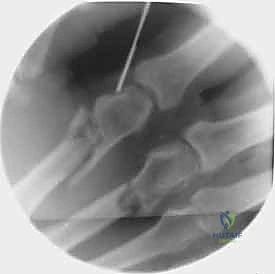

1. التثبيت باستخدام الأسلاك الدقيقة (K-wires)

تُعد هذه الطريقة (Percutaneous Pinning) من التقنيات طفيفة التوغل. يتم إدخال أسلاك معدنية رفيعة جداً عبر الجلد لتثبيت العظم المكسور تحت توجيه الأشعة السينية المستمرة (C-arm) داخل غرفة العمليات.

خطوات التثبيت الجراحي - توثيق بصري (Intraoperative Imaging)

يحرص الدكتور هطيف على توثيق خطوات العمل الجراحي لضمان أعلى مستويات الدقة. نستعرض هنا مجموعة من الصور من داخل غرفة العمليات توضح مدى تعقيد ودقة هذه الجراحات:

تتطلب الجراحة انتباهاً خاصاً للأوتار الباسطة والقابضة والأعصاب الدقيقة المحيطة بالعظام. استخدام تقنيات الجراحة الميكروسكوبية (Microsurgery) يضمن عدم الإضرار بهذه الأنسجة الحساسة.